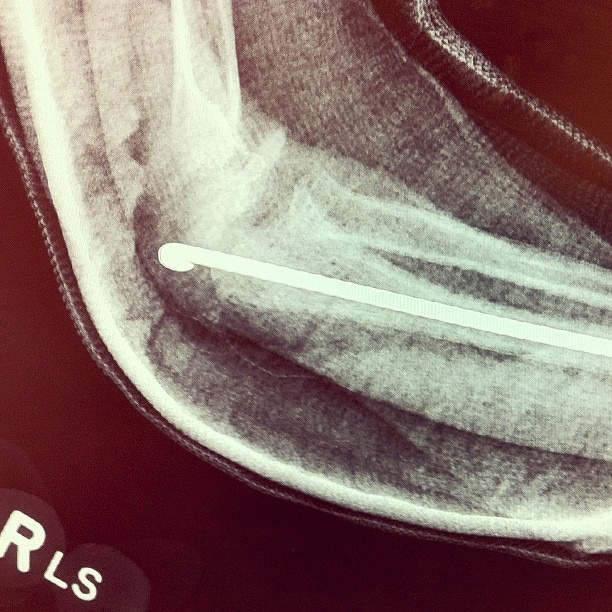

Pin